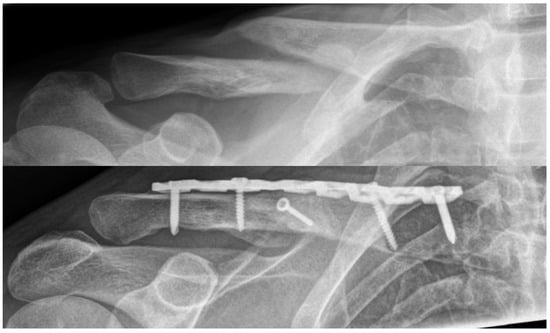

Clavicle Shaft Non-Unions–Do We Even Need Bone Grafts?

3.3. Treatment of Clavicle Non-Unions and Consolidation Rates